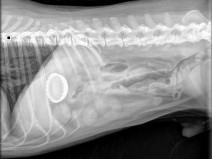

• Journée de travaux dirigés sur l'imagerie du tube digestif

Cette année encore, la journée AFVAC de Capbreton sera placée sous le signe de l'imagerie. Après le succès des TD sur l'imagerie du thorax, nous vous invitons à parfaire vos connaissances en imagerie du tube digestif.

Pourtant si souvent réalisées, les radiographies et images échographiques de l'abdomen sont souvent interprétées trop rapidement, et leur pertinence diagnostique sous-esti...